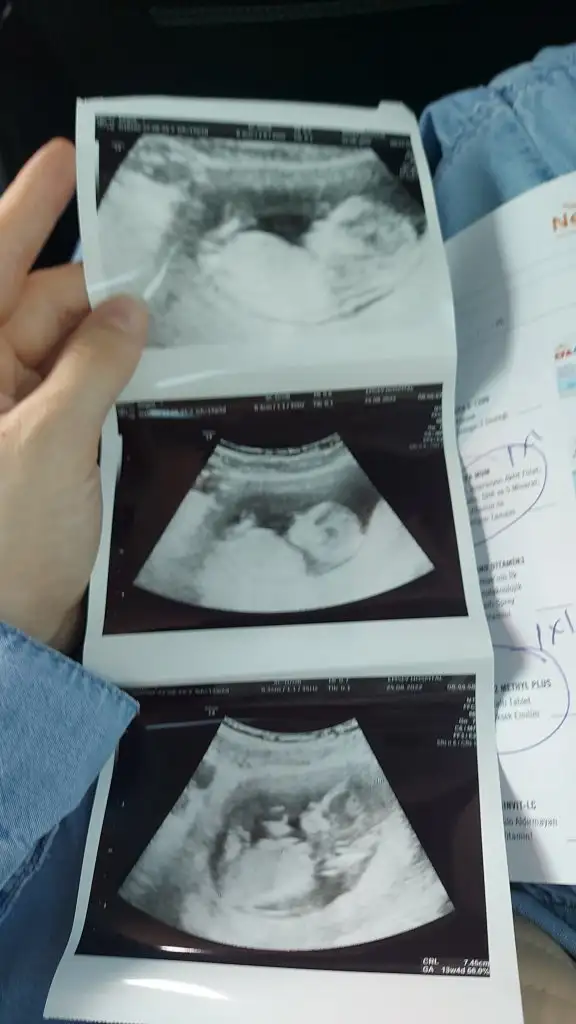

Banada bakarmsnz acaba daha küçük ama işte merak :)net kız, bir sürü nub resmi inceledim int.ten :) sadece cıkıntı degil bebegin omurga pozisyonuna göre de kız

Erkek gibiiBanada bakarmsnz acaba daha küçük ama işte merak :)

Erkeğe benziyor ama kordon da olabilir mi emin olamadım doktor tahminde bulundu muBenimkini de yorumlarmisiniz ? :)

Benim ikizlerime de yorum yapar mısınız?Şimdiden çok teşekkür ederimCanim göremedim pek ama kız gibi geldi